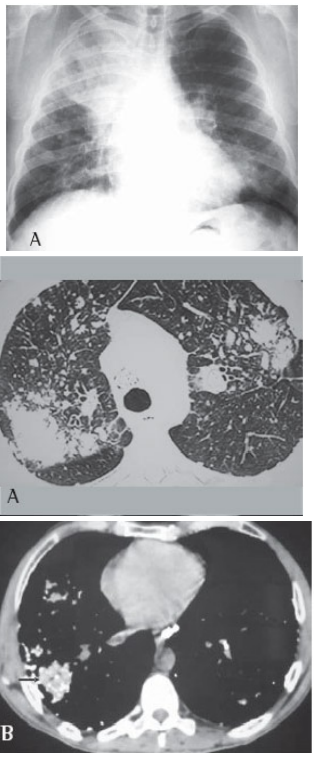

Paciente do sexo masculino, de 44 anos, trabalha há 20 anos em pedreira. Tabagista com uso de 30 maços/ano. Iniciou há cerca de seis meses dispneia progressiva até pequenos esforços, associado com astenia e perda de peso. Foi encaminhado para avaliação. Nega patologias prévias ou uso de medicações. Ao exame, apresenta em regular estado geral, dispneico, saturação periférica de oxigênio 88%, frequência cardíaca 102 BPM, frequência respiratória 25 IRM. Solicitado alguns exames, descritos a seguir: Espirometria:

Pré-broncodilatador: CVF 1,64(48%), VEF1 0,73(26%), VEF1/CVF 45%

Pós-broncodilatador: CVF 1,99(59%), VEF1 0,90 (33%), VEF1/CVF 45%

Qual a conduta inicial para esse paciente?